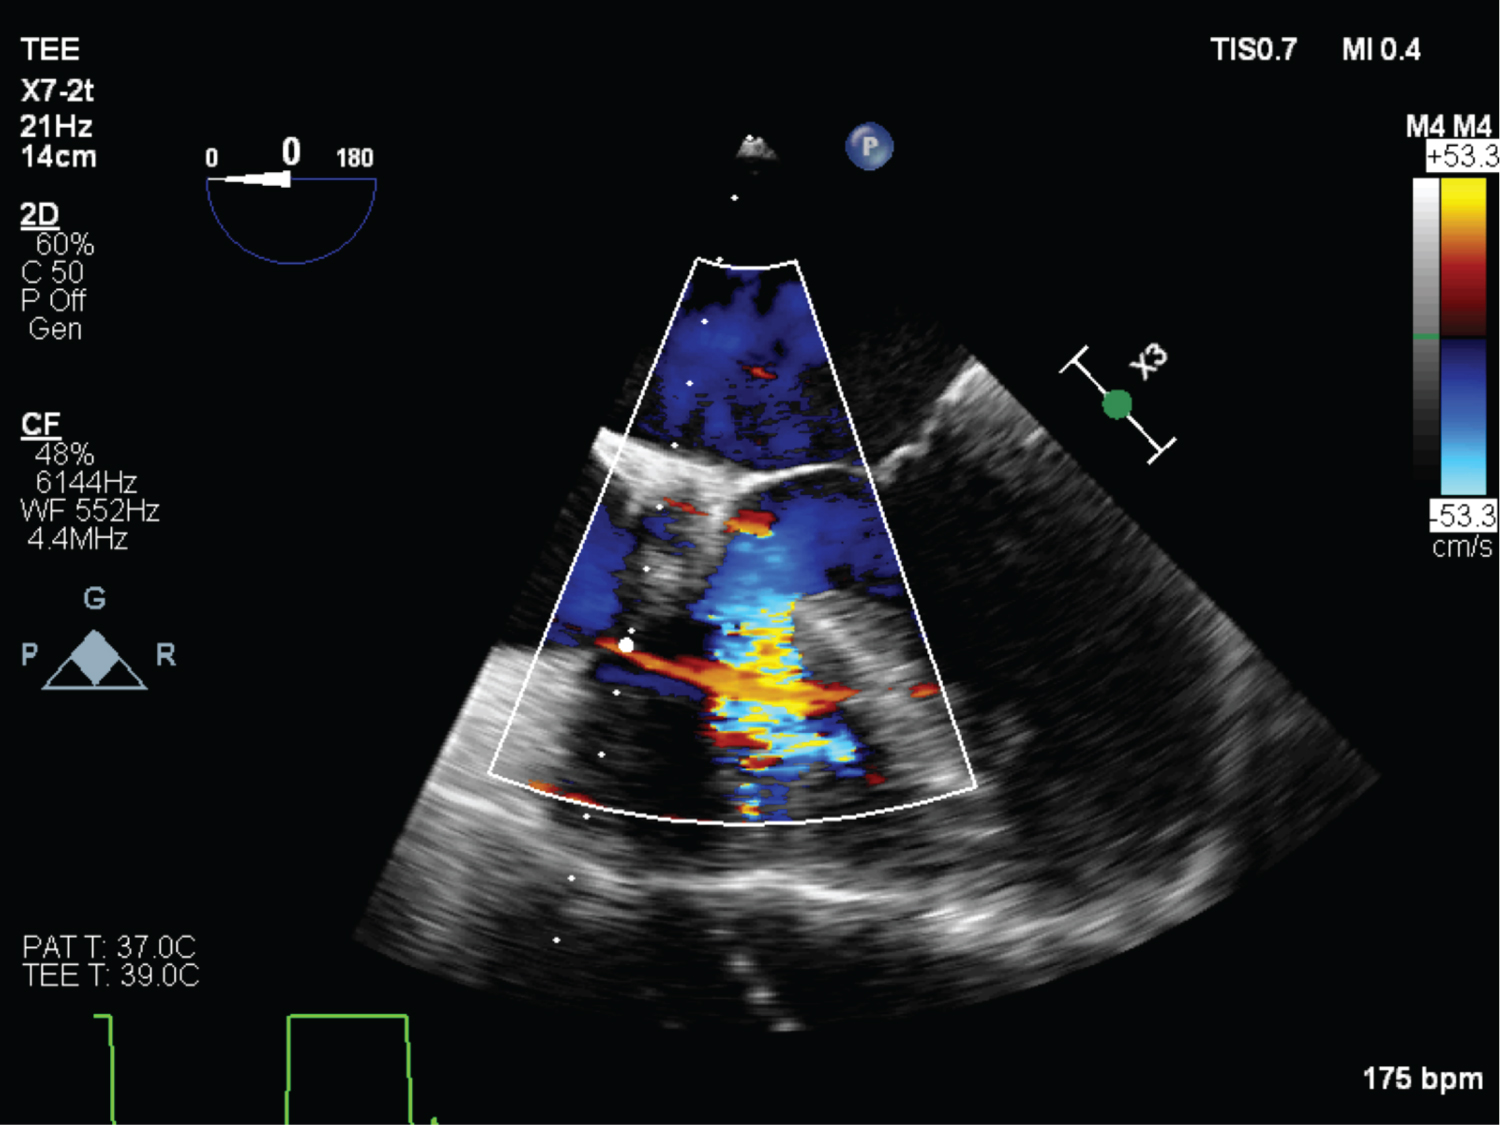

On echocardiography, aneurysmal appearance of the involved sinus and the presence of a “windsock,” protruding into the receiving chamber are characteristic of RSOV [7] (Figure 1, Figure 2, Figure 3, Figure 4 and Figure 5) ( Video 1 and Video 2 ).

Figure 2: (TEE) Mid esophageal RV inflow-outflow view with colour doppler showing RSOV, VSD hypertrophied RV ridge. View Figure 2